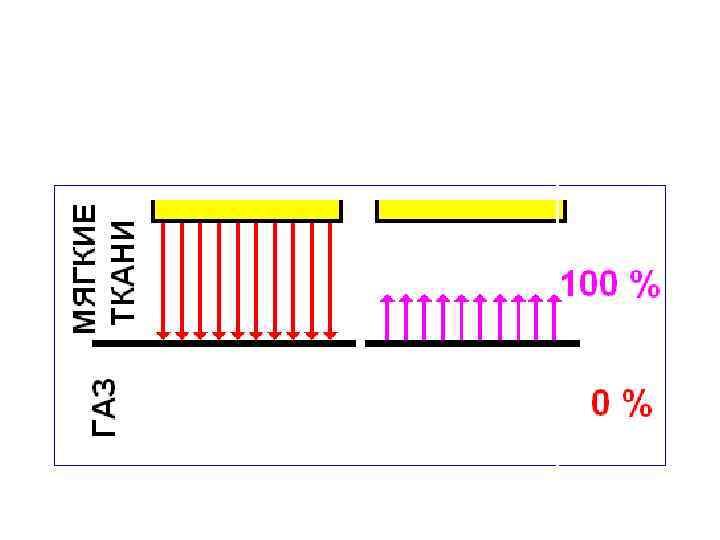

• В однородной среде ультразвуковые волны распространяются прямолинейно и с постоянной скоростью. • На границе сред с неодинаковой акустической плотностью часть лучей отражается, а часть преломляется, продолжая прямолинейное распространение. • Чем выше градиент перепада акустической плотности пограничных , тем большая часть ультразвуковых колебаний отражается.

• В однородной среде ультразвуковые волны распространяются прямолинейно и с постоянной скоростью. • На границе сред с неодинаковой акустической плотностью часть лучей отражается, а часть преломляется, продолжая прямолинейное распространение. • Чем выше градиент перепада акустической плотности пограничных , тем большая часть ультразвуковых колебаний отражается.

Коэффициент отражения • зависит от разности импеданса соприкасающихся сред, т. е. от степени акустической неоднородности граничащих тканей. • чем выше различие в импедансе, тем больше волн отражается.

Коэффициент отражения • зависит от разности импеданса соприкасающихся сред, т. е. от степени акустической неоднородности граничащих тканей. • чем выше различие в импедансе, тем больше волн отражается.

Коэффициент отражения • степень отражения зависит от угла падения волн на граничащую плоскость: наибольшее отражение отмечается при прямом угле падения.

Коэффициент отражения • степень отражения зависит от угла падения волн на граничащую плоскость: наибольшее отражение отмечается при прямом угле падения.